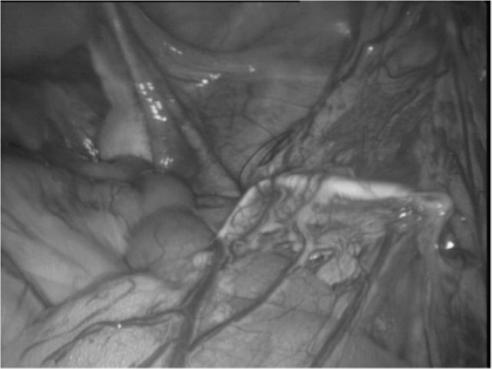

Levonorgestrel-containing intrauterine contraceptive devices, marketed as Mirena (Bayer HealthCare Pharmaceuticals, Inc. Australia) are widely used in contemporary gynecology, primarily as an effective method for contraception and for control of menstrual disorders like menorrhagia and dysmenorrhea. In this article, the authors report 2 cases of Mirena migration following intrauterine insertion by general practitioners (family physicians). In the first case, the contraceptive device had moved to the patient's right iliac fossa just anterior to the cecum and, in the second, within the peritoneal cavity close to the left leaf of the diaphragm. Both patients underwent uneventful laparoscopic retrieval of the devices.

含左炔诺孕酮的宫内节育器,商品名为曼月乐(拜耳医疗保健制药公司澳大利亚分公司),在当代妇科中广泛使用,主要作为一种有效的避孕方法,用于控制月经过多和痛经等月经紊乱。在本文中,作者报告了2例由全科医生(家庭医生)宫内放置曼月乐后发生移位的病例。第一例中,避孕装置移至患者右髂窝,恰好在盲肠前方;第二例中,移至腹膜腔内靠近膈肌左叶处。两名患者均通过腹腔镜顺利取出了节育器。